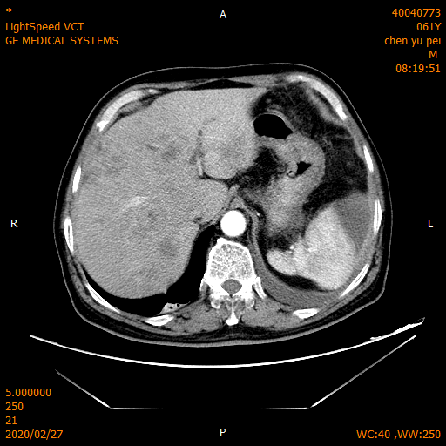

2020-02-04 CT

肝脏多发异常强化灶,考虑转移。

横结肠-降结肠交界处壁增厚强化,请结合消化道检查,腹腔部分肠管扩张积气积液,可见气液平,请结合临床。

2020-02-27 增强CT报告:

肝脏多个略低密度影,考虑转移灶,结合临床;脾脏外缘积液;

胆囊略大;前列腺钙化灶;腹腔积液;左中下腹术后改变;

腹盆腔、后腹膜多发淋巴结,局部肿大;双侧腹股沟小淋巴结。